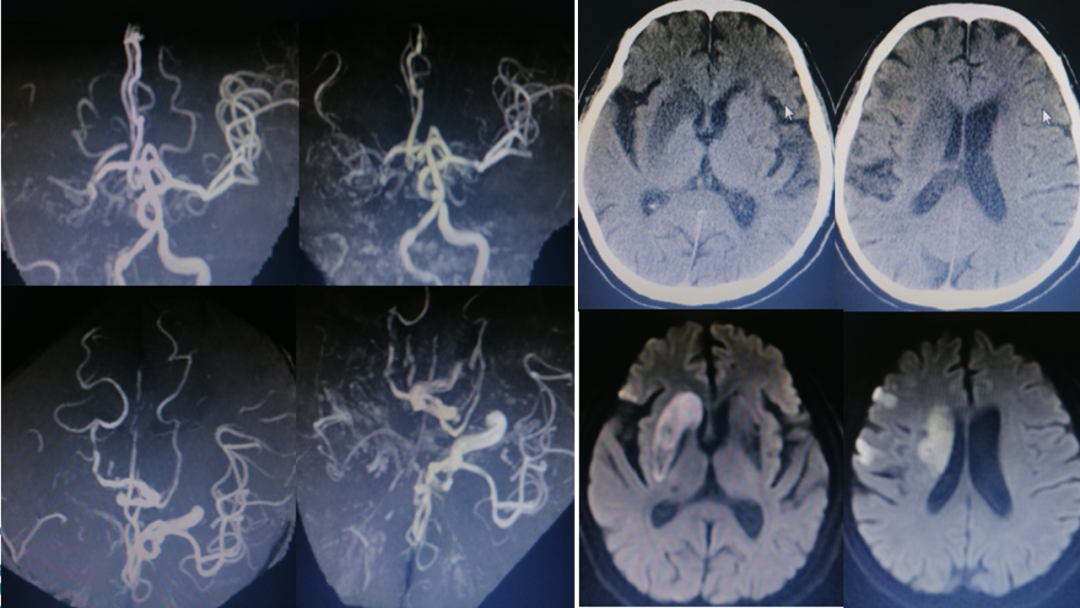

影像诊断

病历夹什么径技·第151期|串联营病历夹:京广连营_https://www.jmylbn.com_新闻资讯_第22张

病历夹什么径技·第151期|串联营病历夹:京广连营_https://www.jmylbn.com_新闻资讯_第23张

病历夹什么径技·第151期|串联营病历夹:京广连营_https://www.jmylbn.com_新闻资讯_第24张

病历夹什么径技·第151期|串联营病历夹:京广连营_https://www.jmylbn.com_新闻资讯_第25张

<<滑动查看下一张图片>>

结论:左侧大脑半球多发梗死灶,T2 flair高信号区域小,左侧颈内-大脑中闭塞,T1 flair提示小出血灶后通过CT排除出血,初步确认为梗死/坏死。